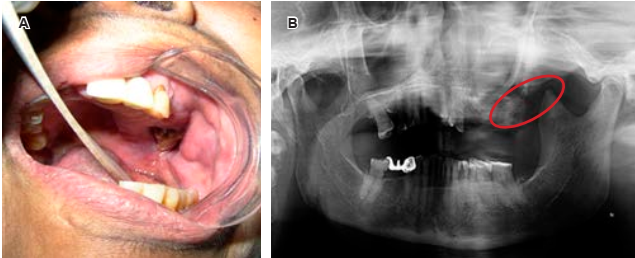

Recientemente se utilizan los bisfosfonatos, medicamentos que sirven de apoyo en el tratamiento. Debido a que inhiben la producción de osteclastos y disminuyen la reabsorción ósea, son utilizados para controlar las metástasis óseas y osteólisis en el cáncer avanzado o descalcificación por cáncer. Existen bifosfonatos orales e intravenosos (ácidos zoledrónico y pamidrónico). Los intravenosos pueden producir el efecto secundario adverso denominado osteonecrosis de los maxilares. El factor de riesgo asociado para que se desarrolle osteonecrosis de los maxilares es traumatismo óseo, siendo las extracciones dentales de tipo quirúrgico las más comunes. En ocasiones, la necrosis ósea se puede presentar de manera espontánea. El odontólogo deberá estar informado de la osteonecrosis asociada a los bifosfonatos y también en contacto con el médico oncólogo.8,9 Se muestran casos de osteonecrosis por en las Figuras 3 y 4.

Figura 3 A y B) Casos de necrosis y exposición ósea maxilar y mandíbula con posterior a extracción dental. C) Caso de necrosis y exposición ósea maxilar de forma espontánea.

Figura 4 A y B) Caso de cáncer de mama presenta necrosis ósea y exposición en el maxilar lado izquierdo, la Rx. Ortopantomografía muestra destrucción trabeculado óseo en el maxilar del lado izquierdo.